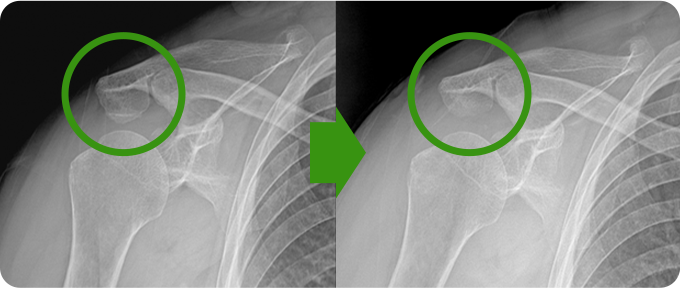

견봉성형술&감압술

견봉성형술과 감압술은 어깨 관절의 충돌을 줄이고 통증을 완화하기 위한 수술적 방법입니다. 견봉성형술은 견봉의 아래쪽 뼈를 다듬어 회전근개와 견봉 사이의 공간을 넓히는 과정으로, 관절의 움직임을 개선합니다. 감압술은 염증을 유발하는 조직이나 점액낭을 제거하여 어깨 관절의 압력을 줄이고 기능을 회복합니다.